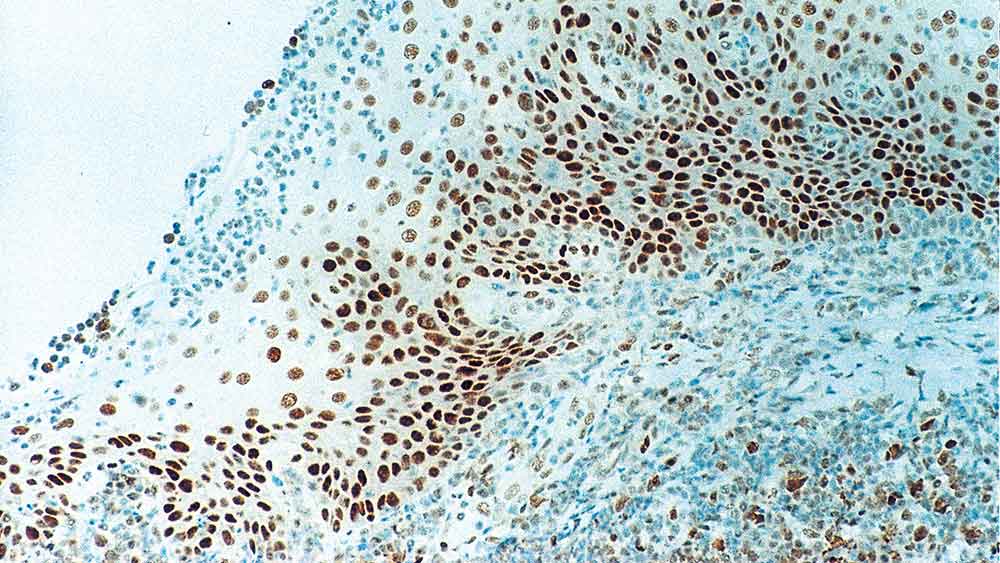

Human tonsil: immunohistochemical staining for Retinoblastoma Gene Protein. Note intense nuclear staining of epithelial cells. Retinoblastoma Gene Protein: clone 13A10

O Retinoblastoma (Rb) é um tumor raro da retina associado com mutações do cromossomo 13. A fosfoproteína nuclear codificada pelo gene supressor do tumor Rb está presente em muitas células e pode regular indiretamente o crescimento celular ativando o fator de transcrição ATF-2.

A ativação do ATF-2 inicia a expressão do TGF-β2, que por sua vez inibe a transcrição dos genes afetando o crescimento celular. A mutação bilateral do gene Rb pode potencialmente desempenhar um papel no desenvolvimento de um número de tumores malignos.

O NCL-RB-358 foi destacado na região terminal-N da proteína do gene Rb.